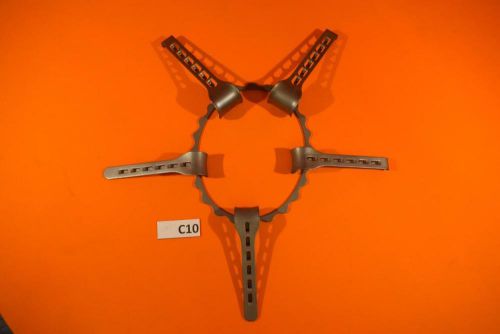

V. Mueller Denis Browne Abdominal Retractor Set Pediatric